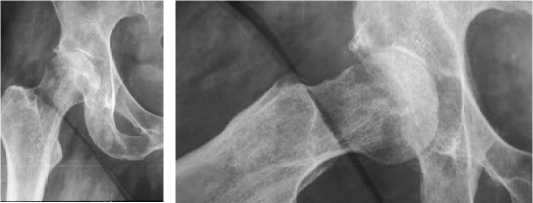

Приводим клинический пример случая двухэтапного хирургического лечения септического коксита с использованием премоделированного цементного спейсера (промышленного производства) из цемента, насыщенного гентамицином (рисунок 1).

б

а

в г д

Рисунок 1 . Случай двухэтапного эндопротезирования тазобедренного сустава у пациента 40 лет, с деструктивной формой правостороннего септического коксита с применением премоделированного цементного спейсера с генатмицином: а - рентгенограмма пораженного сустава; б – компьютерная томография сустава; в - рентгенограмма тазобедренного сустава после установки спейсера на первом этапе хирургического лечения; г -внешний вид премоделированного цементного спейсера тазобедренного сустава (после удаления); д - рентгенограмма тазобедренного сустава с установленным эндопротезом на втором этапе хирургического лечения